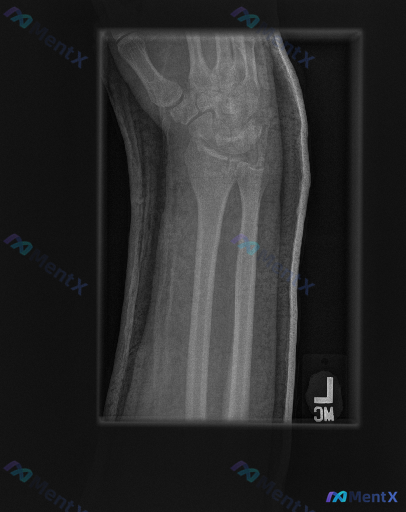

整理到一份左前臂及腕部侧位X光片的影像资料,先和大家同步客观所见的线索: 1. 骨骼方面:桡骨远端背侧和掌侧皮质有连续性中断,可见骨折线涉及关节面,断端有背侧移位、背侧成角的表现,局部有粉碎或压缩改变;尺骨远端(尺骨茎突)处也可见透亮线。 2. 关节方面:桡腕关节的对应关系有改变,随桡骨移位出现背侧...

【病例资料】 影像资料:左侧前臂侧位X光片 临床背景:成人,考虑创伤相关表现 从这张图像中可以注意到一些与正常情况不符的征象,包括骨皮质改变、关节对位、周围软组织等方面的异常。 想先听听大家的第一判断倾向——单看这张侧位片的表现,你更倾向于首先考虑哪类核心异常?

整理到一份右侧腕关节急性创伤后的侧位X光影像分析资料,先和大家同步一下关键发现: - 骨骼方面:桡骨远端可见骨折线,累及关节面,骨折远端向背侧移位、背侧成角,掌倾角完全丧失;尺骨茎突基底部也有骨折线。 - 关节方面:桡腕关节对合关系改变,关节面不平整,有碎块;近排腕骨(如月骨)随桡骨向背侧移位,腕骨...